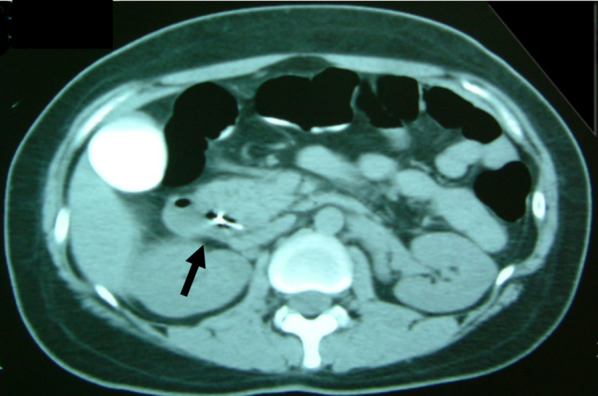

A 30-year-old woman was transported to our hospital by ambulance due to epigastric pain. A laboratory analysis revealed the following: white blood cells, 4000/mm3; total bilirubin, 3.0 mg/dL; alkaline phosphatase, 640 IU/L; GOT, 395 IU/L; GPT, 746 IU/L; and amylase, 37 IU/L. Abdominal CT demonstrated multiple gallbladder (GB) stones without inflammation of the GB; the diameter of the common bile duct (CBD) was 10 mm. ERCP was performed under the suspicion of CBD stones. Bile duct cannulation was easily performed. Cholangiography revealed no apparent CBD stones. Although EBD is not routinely carried out in this situation, we carefully performed EBD due to the suspicion of CBD stones, and carefully taking the clinical course into consideration. Before the procedure, a dilatation balloon (Hurricane RX Rapid Exchange, Boston Scientific, MA, USA) was inflated as a precaution in order to check the condition of the balloon. The dilatation balloon was then passed over the guidewire and located at the site of the biliary sphincter. The balloon was inflated to 2 atmospheres of pressure. After the procedure, the balloon suddenly burst. We were unable to remove the EBD catheter because the balloon was caught at the biliary sphincter (Figs. 1, 2). A computed tomography (CT) scan showing the burst balloon located at the site of the biliary sphincter (Fig. 3). Finally, we had to perform surgical intervention to remove the EBD. We made an incision at the pylorus, and then we manually pulled the EBD catheter through this incision, as shown in Fig. 4a, b. The broken catheter was successfully removed without injuring the biliary sphincter. Cholecystectomy, CBD exploration, and then removal of the CBD stone were performed. A T-tube was inserted for drainage. Intra-operative cholangiography revealed no residual stones and no biliary sphincter abnormality (Fig. 5). The burst balloon of the EBD catheter is shown in Fig. 6. The patient was discharged without any complications after removal of the T-tube on post-operative day 14.